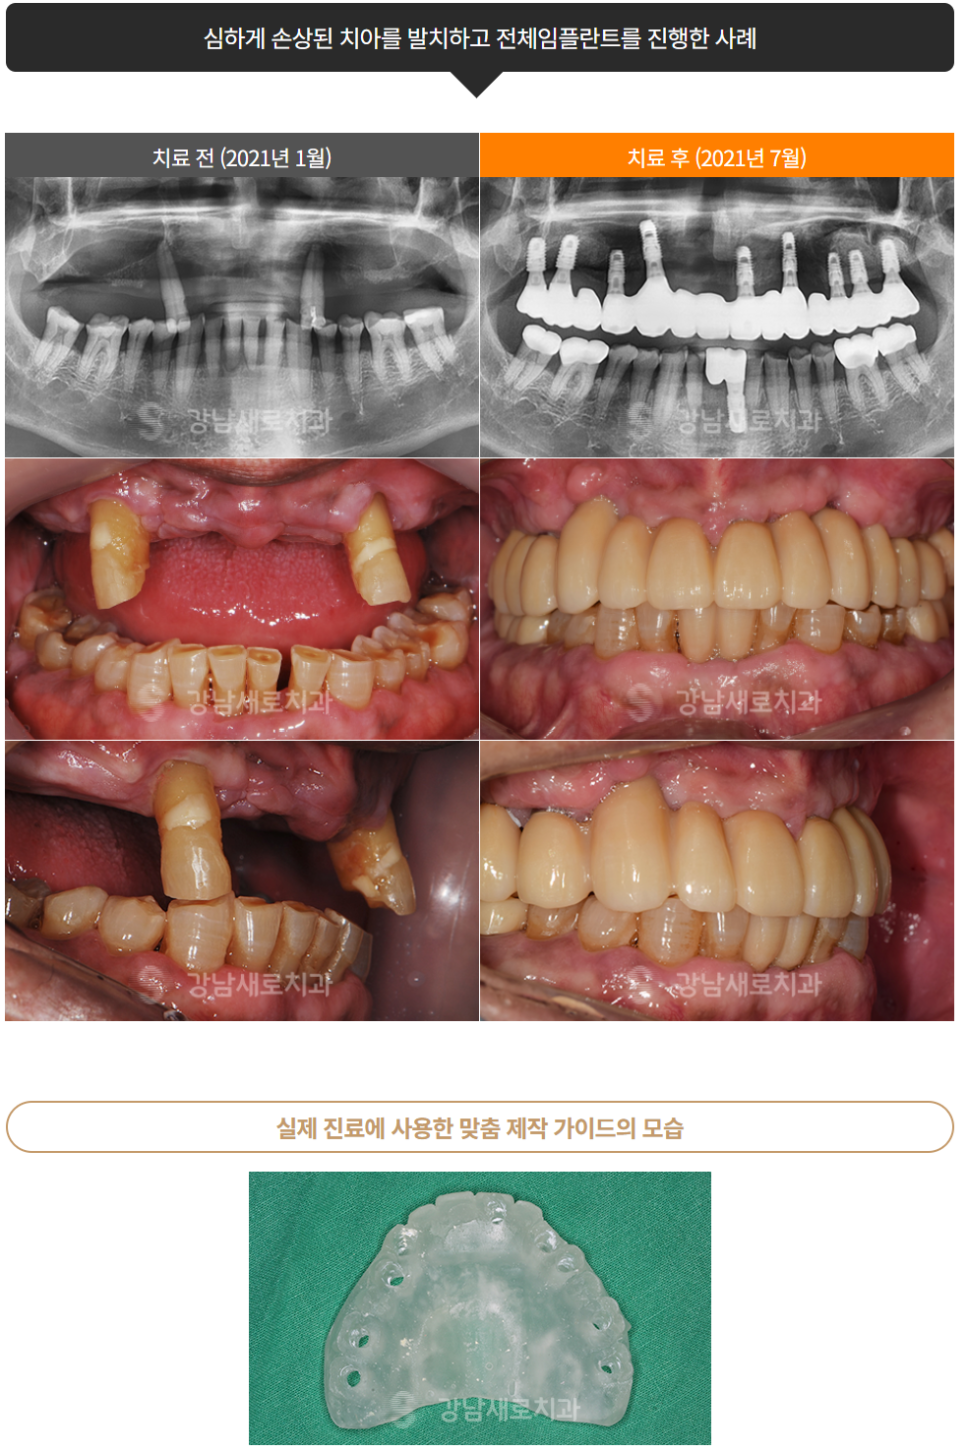

강남새로치과

“네비게이션 임플란트 결과”

⑤ 개별 맞춤형 수술 가이드 제작 : 모의수술 결과를 바탕으로 맞춤형 수술 가이드를 제작합니다. 가이드를 착용하면 식립 과정에서의 오차 발생과 부작용 발생 가능성을 효과적으로 줄이는 데 큰 효과가 있습니다.

이 때 부작용 발생 가능성이 줄어들면 동시에 재수술로 이어질 가능성 역시 줄어들게 됩니다. 이는 임플란트 수명 연락에 효과적이라 할 수 있습니다.